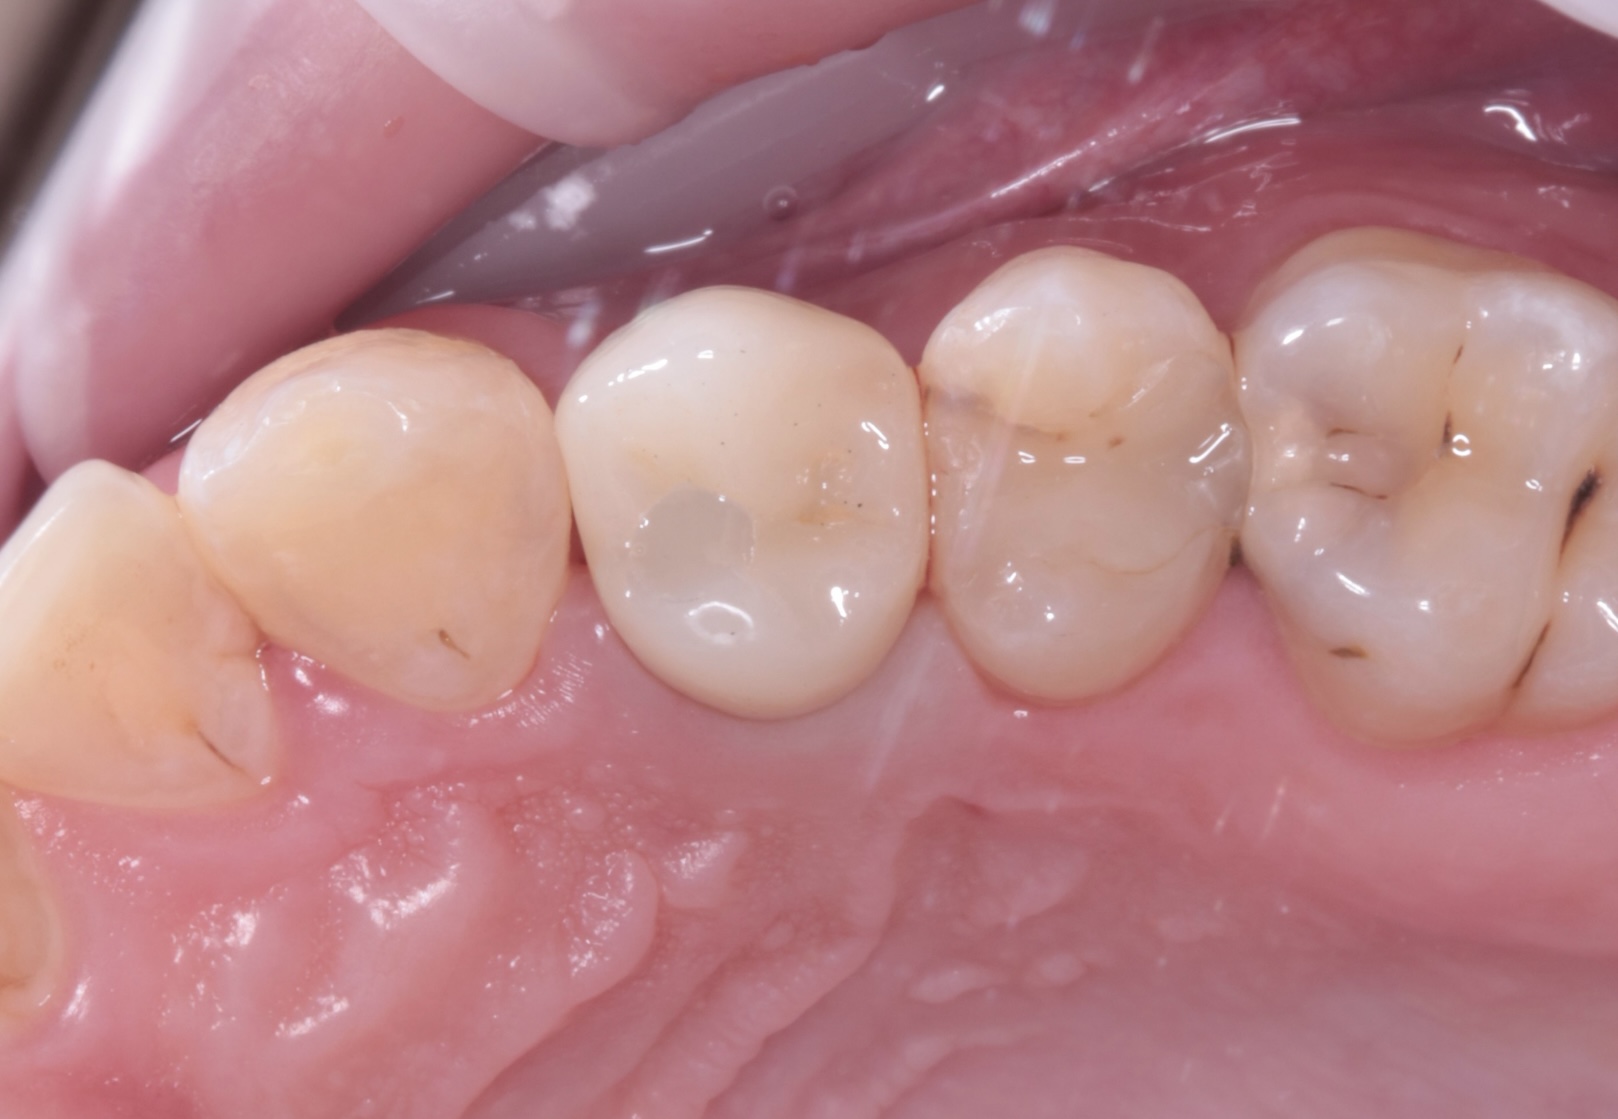

Наши работы